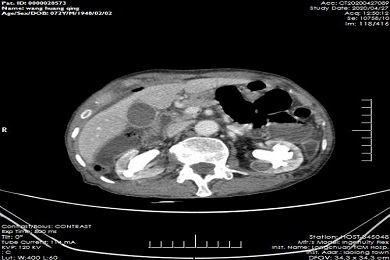

【组团帮扶】龙川县中医院完成首例腹腔镜肝癌根治术,深中医院技术帮扶谱新篇